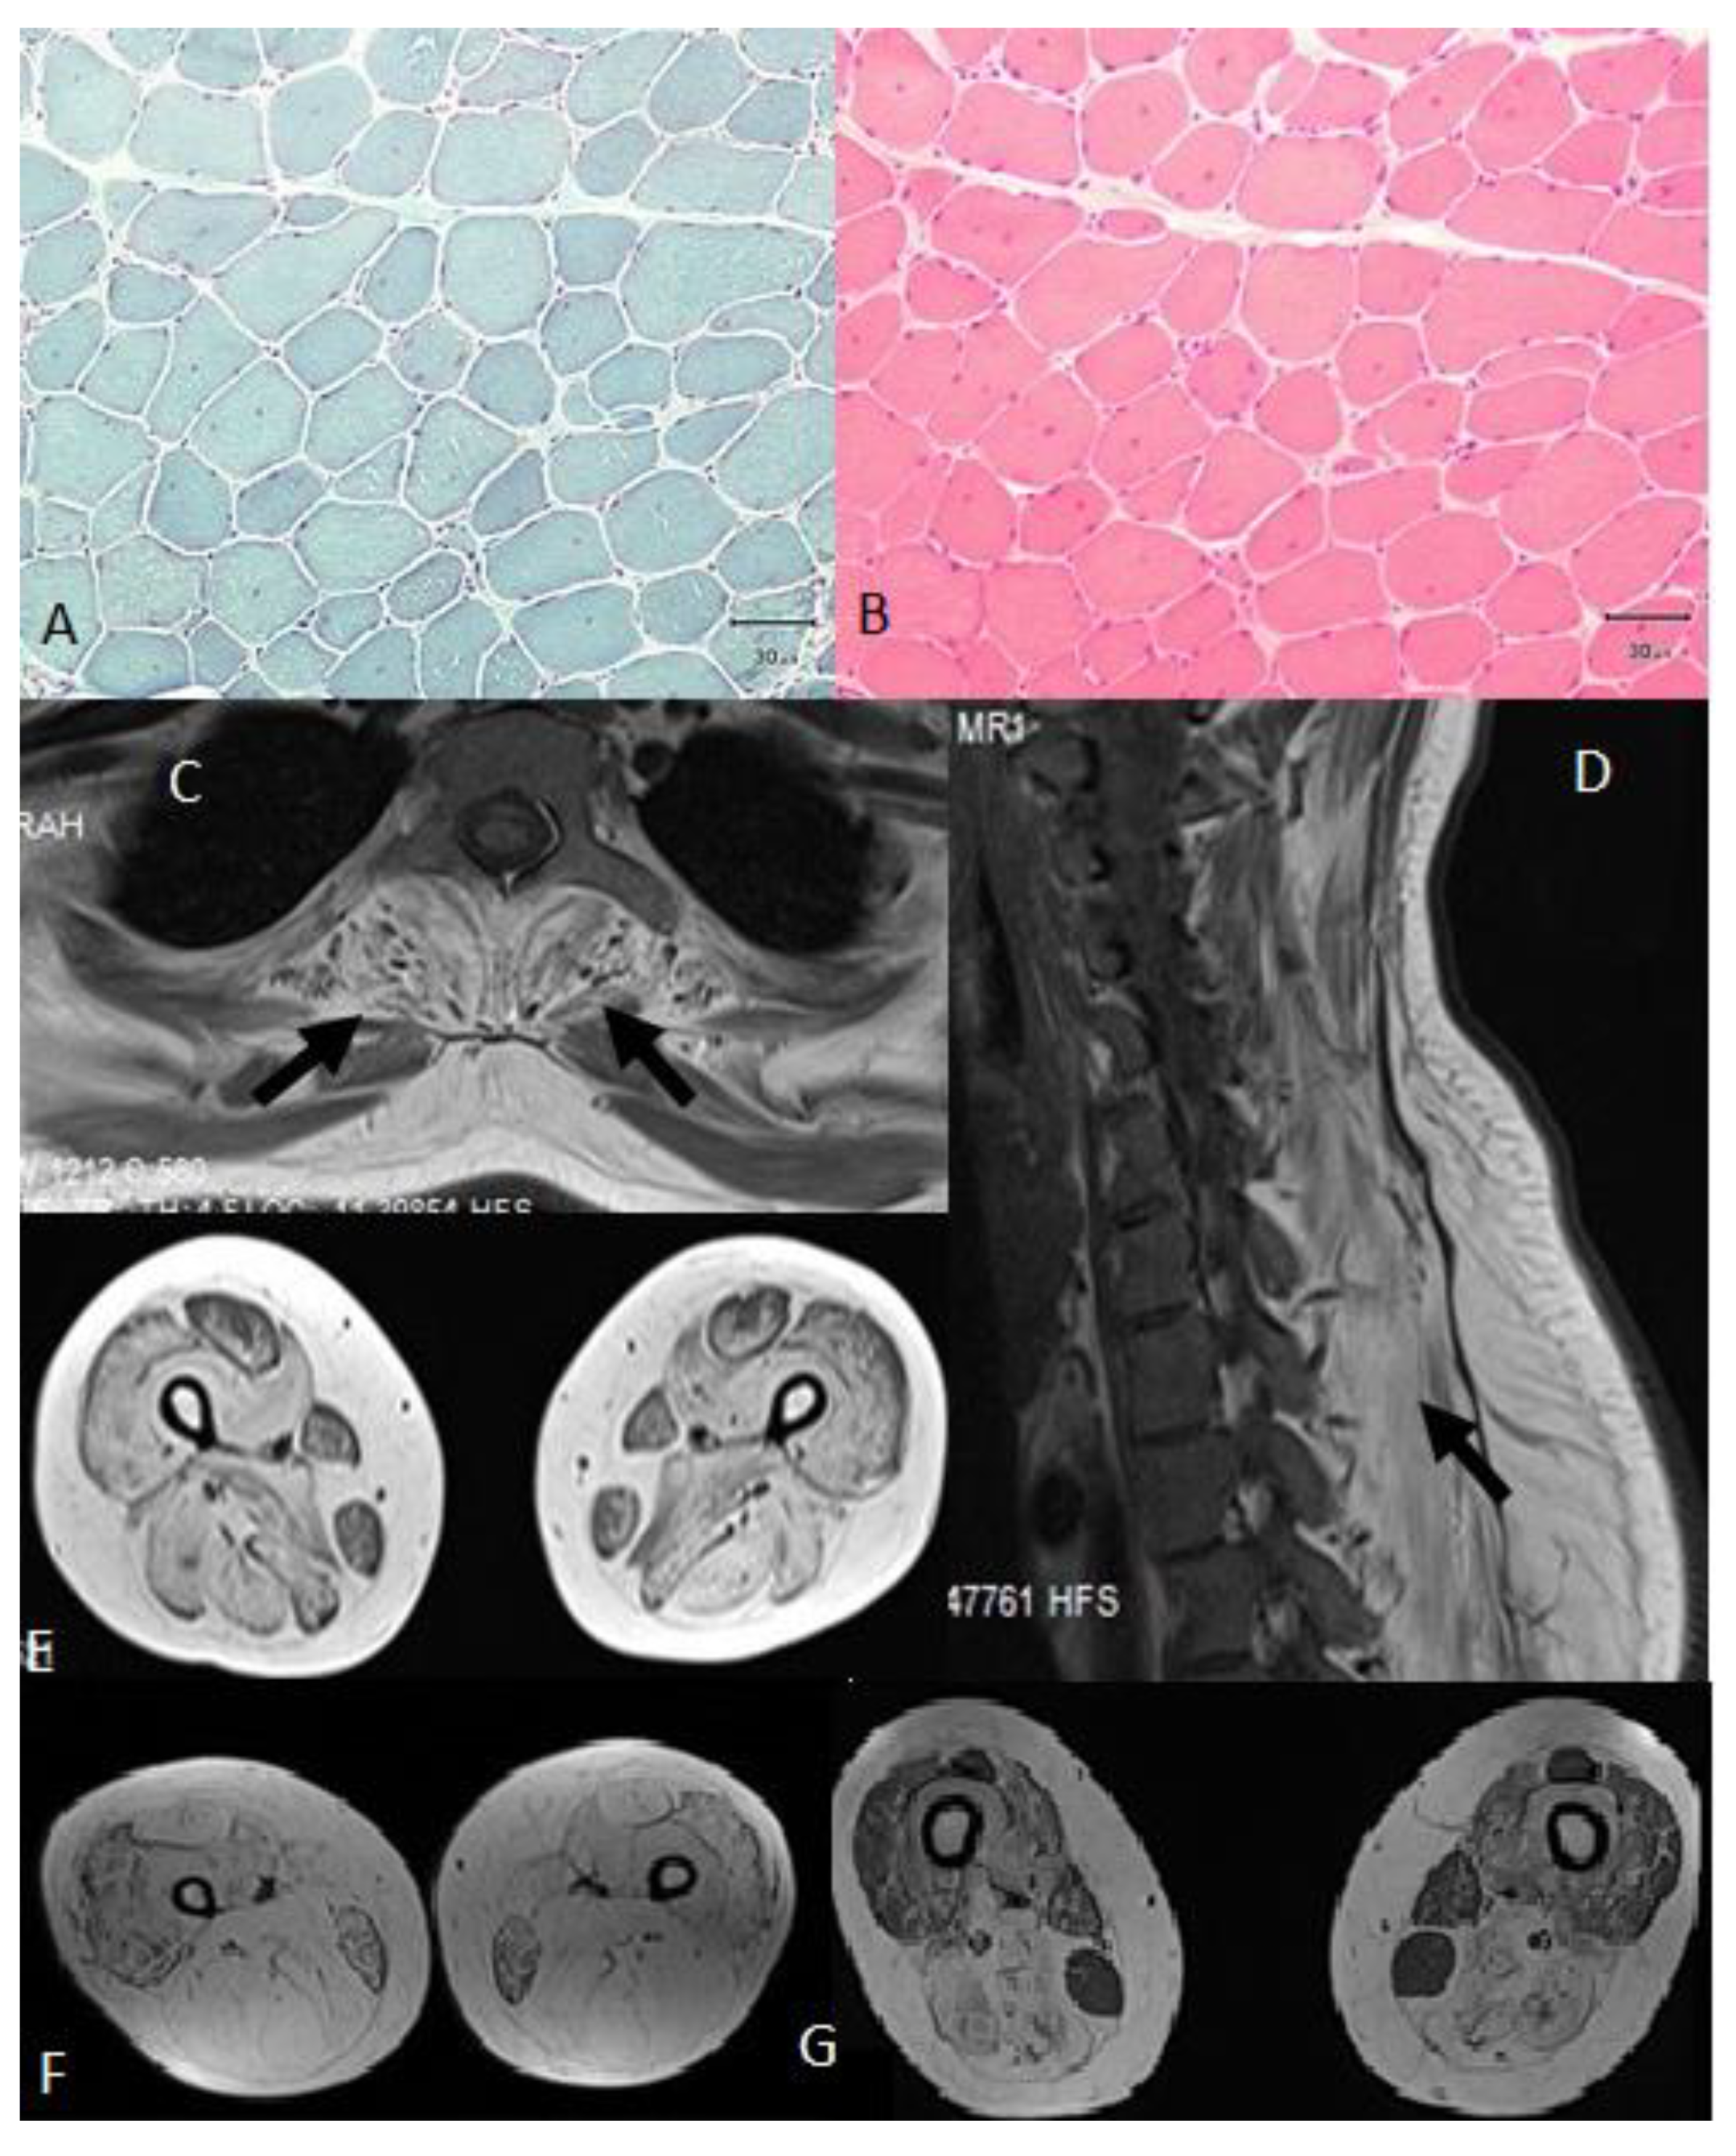

| A | 37 | 6 | Normal | Difficulty in walking | Yes | Ptosis, neck flexor 2/5, upper proximal (3/5), distal (4/5), lower proximal (2/5), distal (4/5), paraspinal and abdominal muscle weakness | Yes | Yes (38) | 1379 | Myopathic, high jitter in SF-EMG | Dystrophic, increased number of internal nuclei, a few angular atrophic fibers | This study |

| B | 38 | 26 | Normal | Difficulty in climbing stairs | Yes | Bilateral ptosis, neck flexors 3/5, upper proximal (4/5), upper distal 4/5 lower proximal (3/5) and distal (4/5), paraspinal and abdominal muscle weakness | Yes | No | 3290 | Myopathic and high jitter in SF-EMG. 10% decremental response in Trapezius muscle on RNS | Dystrophic increased number of internal nuclei, a few angular atrophic fibers | This study |

| C | 40 | Early childhood | Delayed—Age of onset for walking 2.5 years | Delayed walking, slower than her peers | Yes | Mild ptosis, nasal speech, tongue weakness, upper proximal 2/5, distal 3/5; lower proximal 1-2/5, distal 2/5, paraspinal and abdominal muscle weakness | Yes | Yes (35) | 4980 | Myopathic, spontaneous pathogenic activity, high jitter in SF-EMG. 8.7% decremental response in trapezius on RNS | Dystrophic, increased number of internal nuclei, a few angular atrophic fibers | This study |

| D | 27 | Early childhood | Delayed | Difficulty in climbing up stairs | Yes | Bilateral mild ptosis, upper proximal (4/5), distal (5/5), lower proximal (3/5), distal (4/5), paraspinal, and abdominal muscle weakness | Mild | No | 6200 | Myopathic, spontaneous pathogenic activity, high jitter in SF-EMG. 12% decremental response in trapezius on RNS | Dystrophic, increased number of internal nuclei, a few angular atrophic fibers | This study |